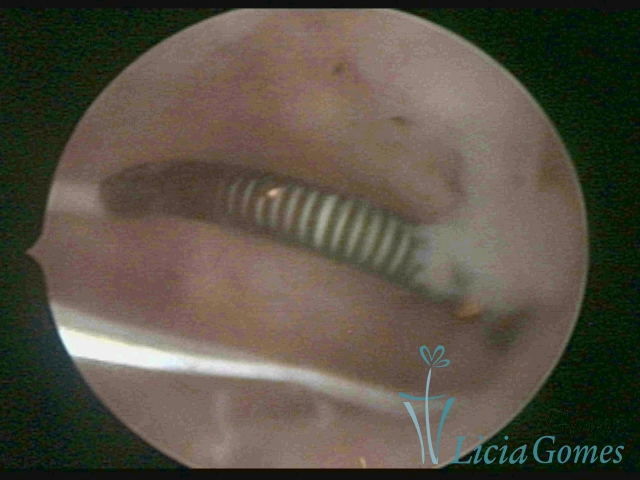

Cavidade com o Mirena®, sendo retirado sob visão direta